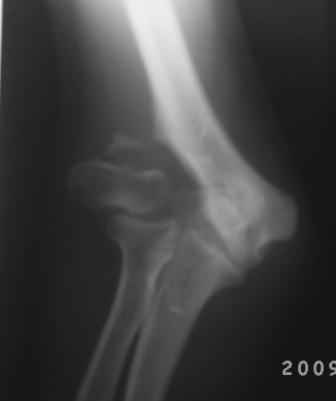

Уважаемые коллеги! Обратился больной 17 лет с жалобами на деформацию пр. локтевого сустава.

Травму получил 7 лет назад. Локально: вальгусная деформация л/с под углом 45гр., сгибание -30, разгибание-170гр., наружный мышелок плеча под пальцами подвижен, что интересно- мышелок плеча при пронации и супинации п/плечья вместе с головкой луча поднимается и опускается( см снимки).

Для интереса представляю снимки.

Вы очень конкретно и правильно поставили вопросы и очень аргументированно анализировали, смысл мне понравился, дело в том что у меня был случай 4-года назад. Б-ная 18 лет, травму получила в детстве, клиника точно такая, только движения в плече-лучевом суставе была сохранена, произведена клиновидная надмышелковая остеотомия, фиксация спицами и тогда была наложена гипсовая повязка на 1,5месяца, разработка движений начался очень хорошо, и она уехала в другой город, где оказывается удалили спицы и она доволно результатом.( ложный сустав латераль. мышелка так и осталось и ей не мешает!)

Кликните для загрузки файла 1.jpg

57KB (59263 bytes)